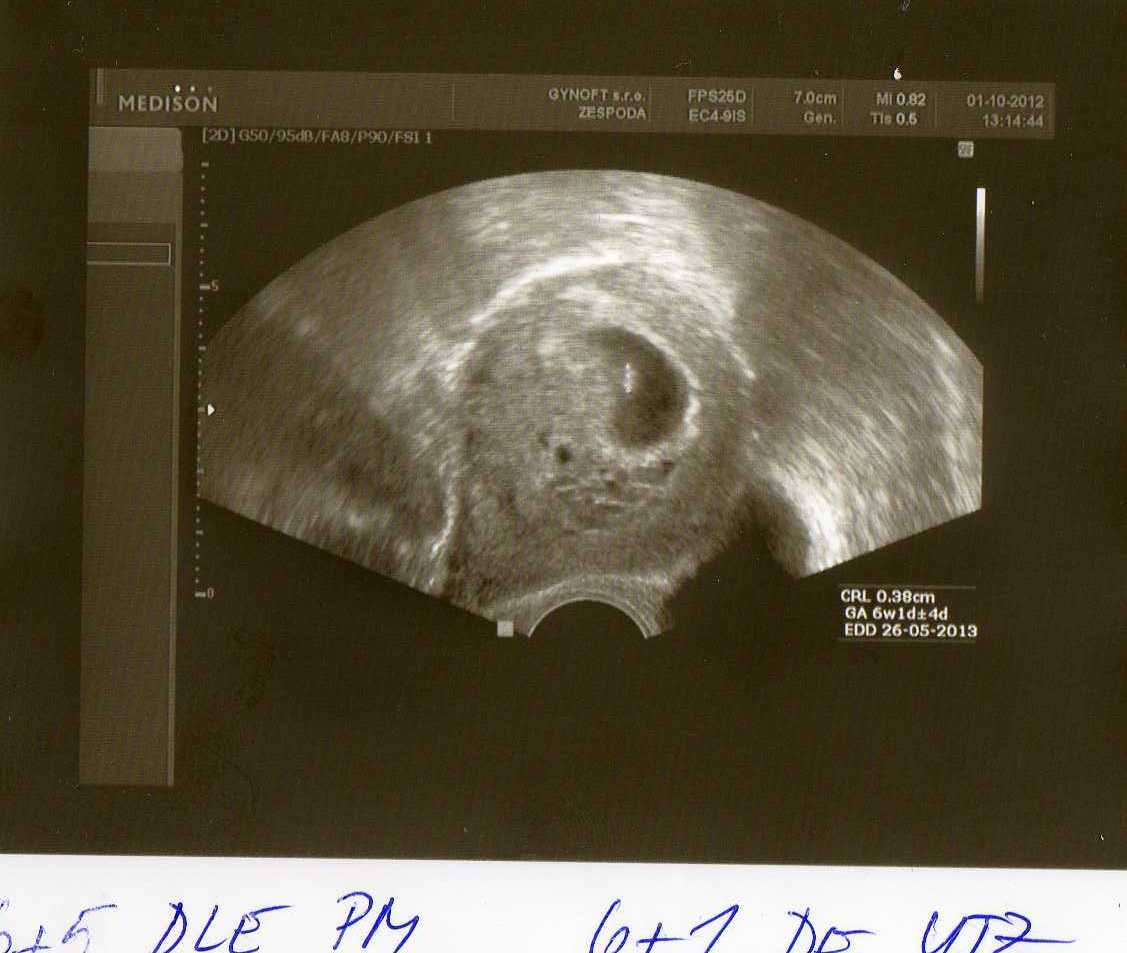

holky tak před 13h na mě myslete prosím 😉 jen se zeptám....nevíte jaká je pravděpodobnost opakovaného zamlklého těhu když genetika je OK????Blbé otázky já vím..ale prostě já mám tak obrovský strach.... 😒